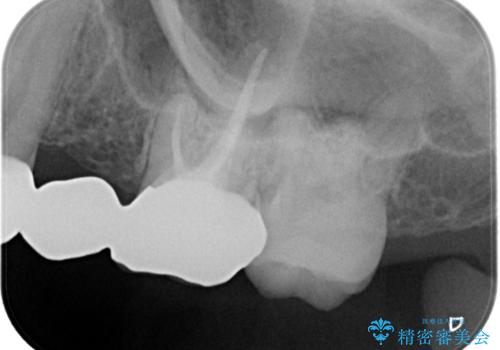

- 昔装着したかぶせ物が、不自然なのでやりかえたいとのことで来院されました。

前歯にレジン前装冠(保険内)が装着されており、自然な透明感がありません。

また奥歯にまたがるブリッジも金属のもので、適合もよくありませんでした。

オールセラミックによるやりかえを行いました。